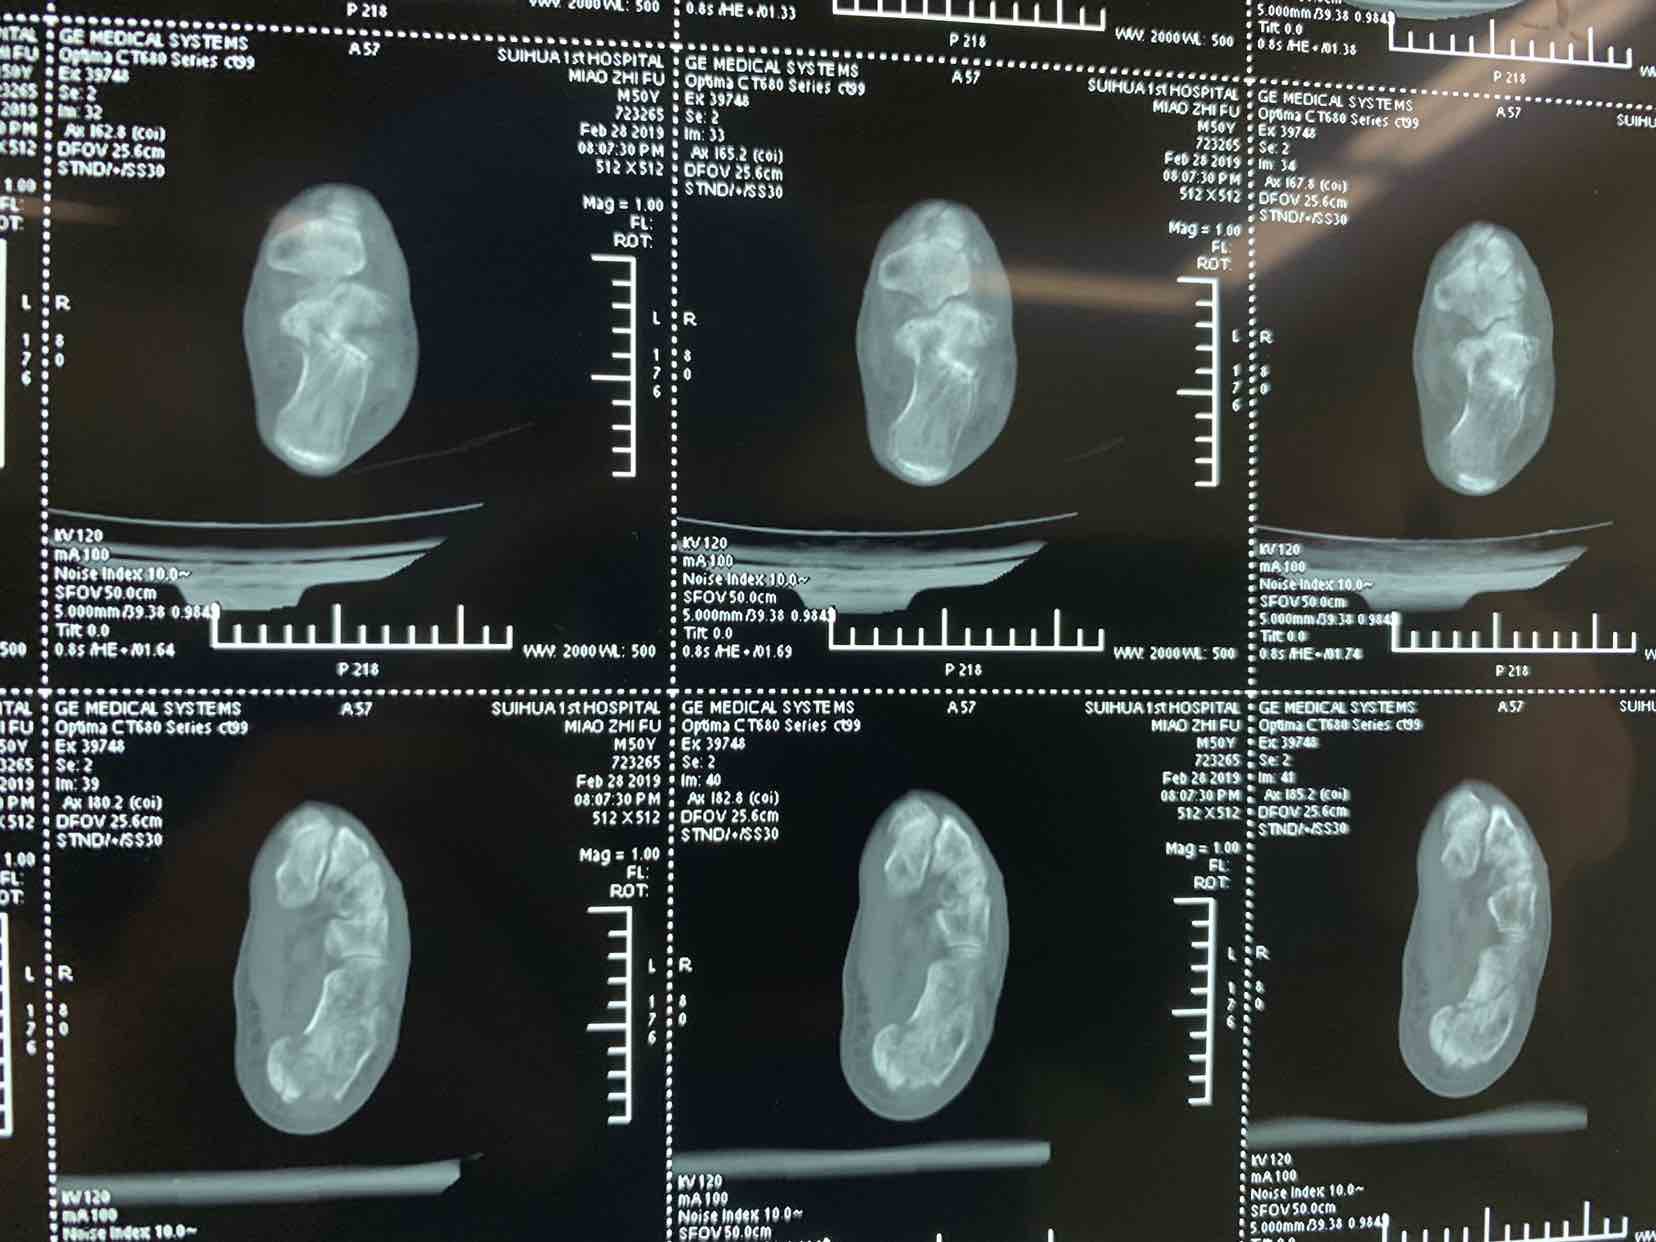

患者因自二米高处坠落,左侧足跟肿痛畸形活动受限一小时收入院。患者于一小时前不慎自二米高处坠落。当即左侧足跟肿痛。畸形。不能下地走路。急来诊。门诊拍片提示左侧跟骨骨折。门诊以左侧跟骨骨折收入院。

查体见左侧左跟局部肿胀。足弓消失。跟骨横径增宽。局部畸形。活动受限。不能下地走路。局部皮下淤血。拍片提示左侧跟骨粉碎性骨折。断端移位。